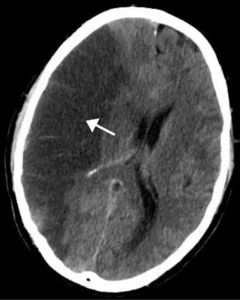

A stroke can happen suddenly and without any warning. It occurs “when blood flow to the brain ceases, leading to the death of brain cells in that area,” according to Healthline.

A transient ischemic attack (TIA), commonly known as a “mini-stroke,” occurs when blood flow to the brain is temporarily obstructed, resulting in stroke-like symptoms that usually last for a few minutes or hours. TIAs should never be overlooked.